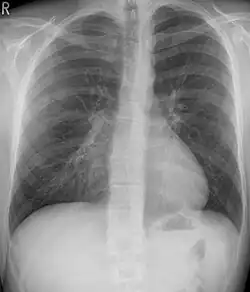

Pectus excavatum

This condition is often called "funnel chest" and is observed as depression of the anterior chest at the xiphisternum. Pectus excavatum is commonly unilateral and, therefore, can lead to asymmetric distribution of thoracic organs. Therefore, a mediastinal shift can be seen in severe cases. Radiographic features include a leftward deviation of the heart and deformed third to seventh ribs. Patients often present with exercise tolerance, cardiac arrhythmias, and heart murmur.[18]